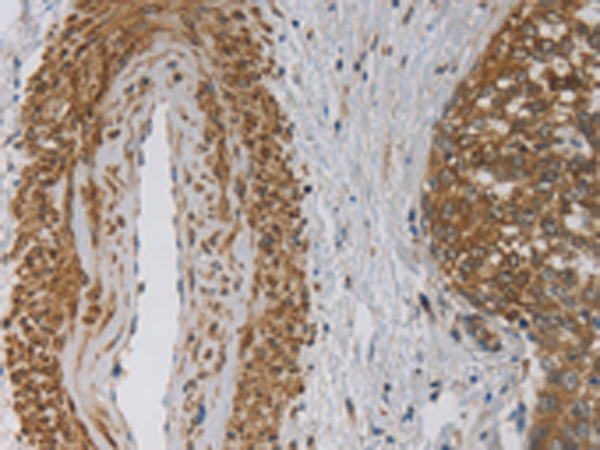

分类: 科研抗体货号: P07246别名: LIT; DCR1; TRID; CD263; TRAILR3; TRAIL-R3; DCR1-TNFR应用: IHC反应种属: Human